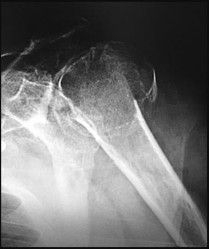

A 12-year-old obese boy presents with left hip pain and an obligate external rotation of the hip during flexion. A radiograph is shown below. What is the most appropriate initial management for the condition demonstrated?

Explanation

The clinical presentation and radiograph represent a stable Slipped Capital Femoral Epiphysis (SCFE). The gold standard for initial management of a stable SCFE is in-situ pinning, typically utilizing a single partially threaded cannulated screw placed in the center-center position of the epiphysis to prevent further slip and promote physeal closure.